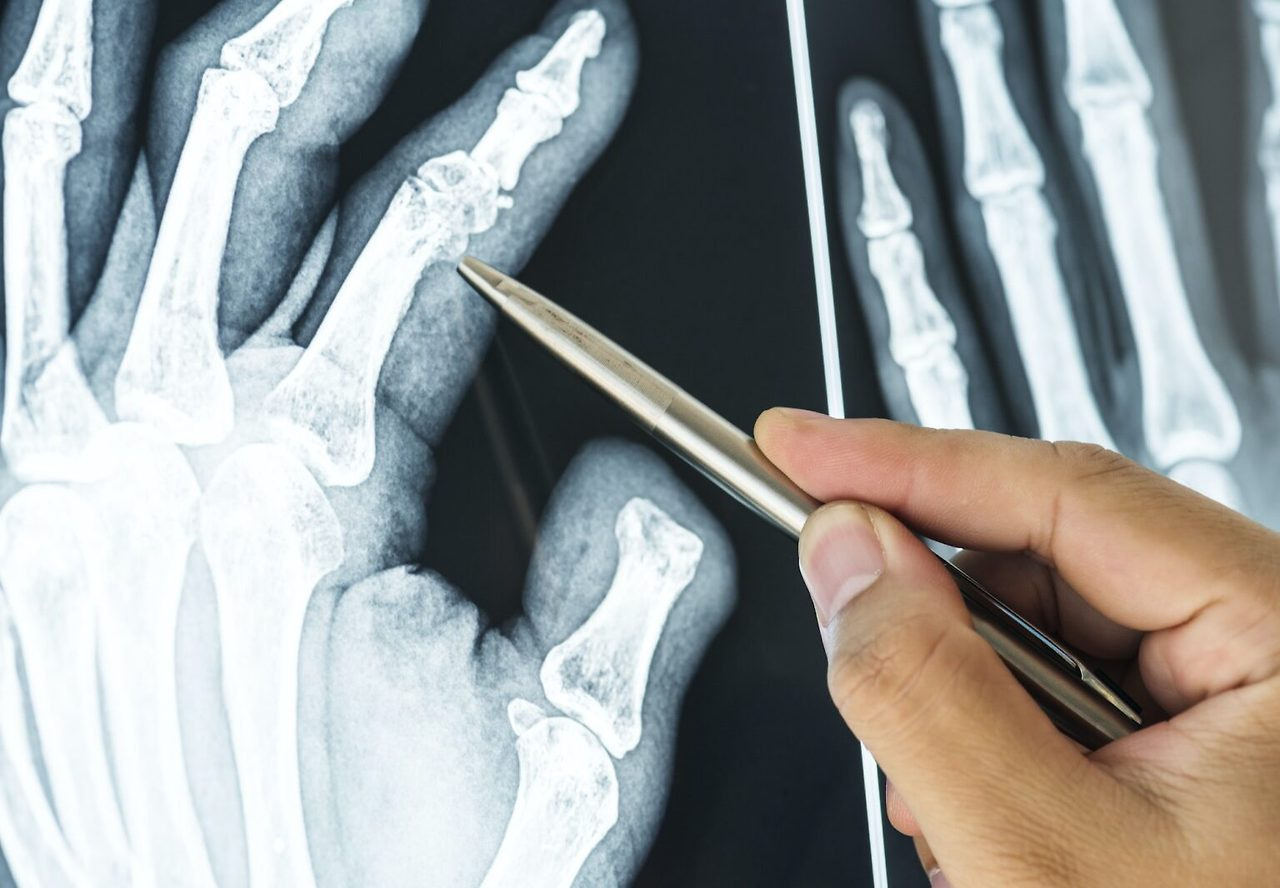

하지만 “부러진 뼈도 언젠가는 붙겠지” 하며 막연히 방치하기보다는, 적절한 치료와 재활 과정을 거쳐야 빠르고 건강하게 회복할 수 있습니다. 본 포스팅에서는 발가락 골절과 손가락 뼈에 금이 갔을 때 손가락 골절 완치기간과, 엄지발가락 뼈에 금이 가면 발가락 완치기간, 그리고 깁스나 스플린트 사용법 및 수술 여부 등 다양한 정보를 자세히 살펴보겠습니다.

- X-ray 촬영: 기본적으로 뼈 상태를 확인하기 위해 X-ray 촬영이 이루어지며, 병원에 따라 2~5만 원 내외의 비용이 들 수 있습니다.

발가락 골절 및 손가락 뼈 골절은 사소해 보이지만, 제대로 관리하지 않으면 장기적인 통증이나 기능 저하, 다시 부러질 위험까지 생길 수 있는 부상입니다. 깁스나 스플린트를 통한 비수술적 치료부터, 핀 고정 등 수술적 방법까지 각 상황에 맞는 치료가 이루어지며, 그에 따라 회복 기간도 달라집니다.

발가락 골절은 대체로 6~8주 정도면 깁스를 풀 수 있고, 스플린트 사용 시에는 4주 정도가 소요되곤 합니다. 하지만 복합 골절이나 나이가 많아 골밀도가 낮은 분이라면, 더 긴 시간이 필요할 수 있습니다. 손가락 골절 또한 비슷한 회복 패턴을 보입니다.